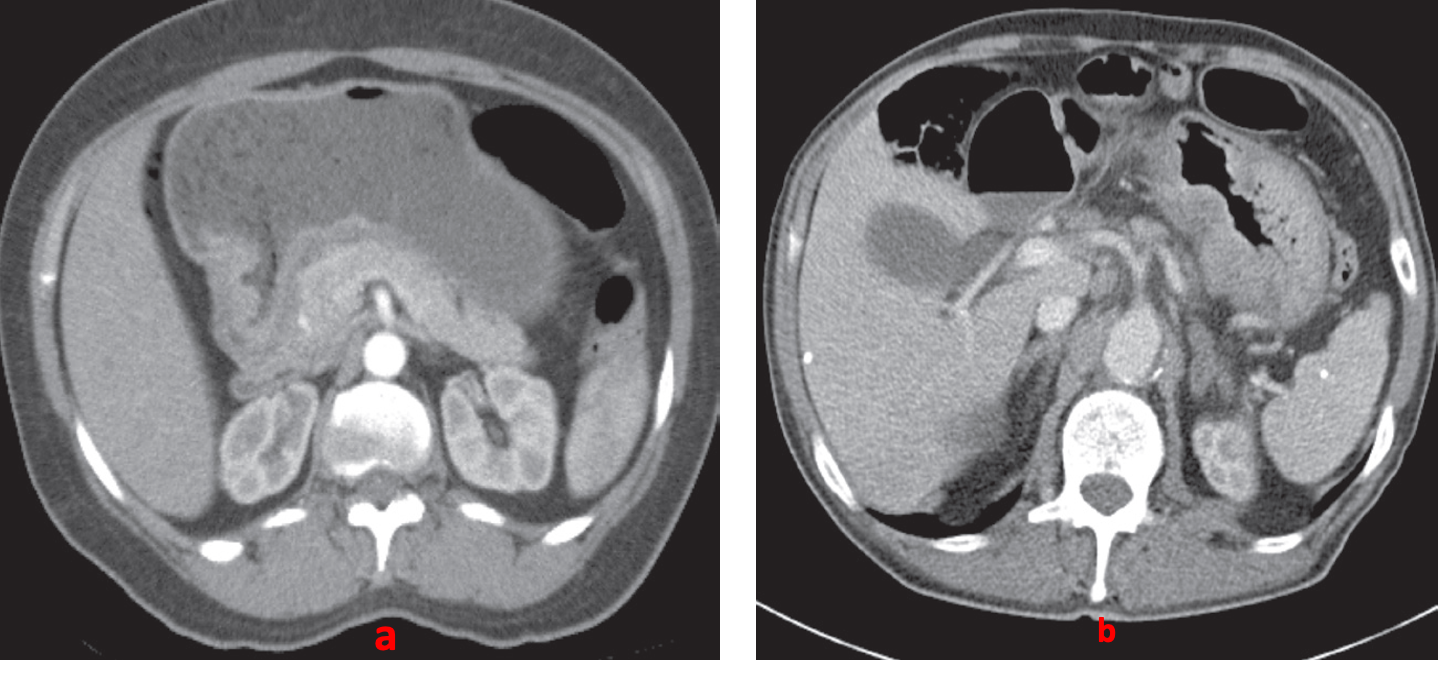

- (A) A focal ulcer is seen arising in the antrum.

- (B) In a different patient, there is diffuse thickening of the wall of the stomach. Several lymph nodes and a liver metastasis are also seen.